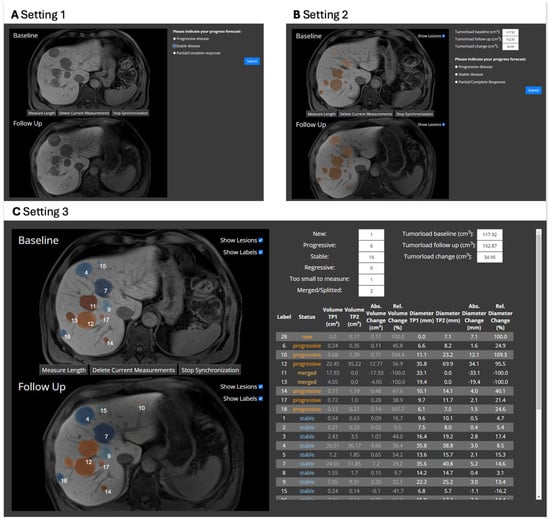

| Metric | Setting 1 | Setting 2 | Setting 3 | p-Value |

|---|---|---|---|---|

| Median decision time in s (IQR) | 13.8 (9.2–21.8) | 14.4 (10.3–24.0) | 23.8 (14.2–42.8) | <0.001 |

| Accuracy in % (SD, range) | 88.7 (SD 11.0, range 67–97) | 90.6 (SD 8.7, range 73–97) | 90.1 (SD 6.1, range 80–97) | 0.72 |

| Precision in % (SD, range) | 81.6 (SD 9.5, range 63–89) | 83.6 (SD 6.4, range 72–89) | 83.4 (SD 5.8, range 73–89) | 0.72 |

| Recall in % (SD, range) | 91.9 (SD 8.7, range 74–98) | 92.9 (SD 7.2, range 78–98) | 90.7 (SD 9.4, range 71–98) | 0.30 |